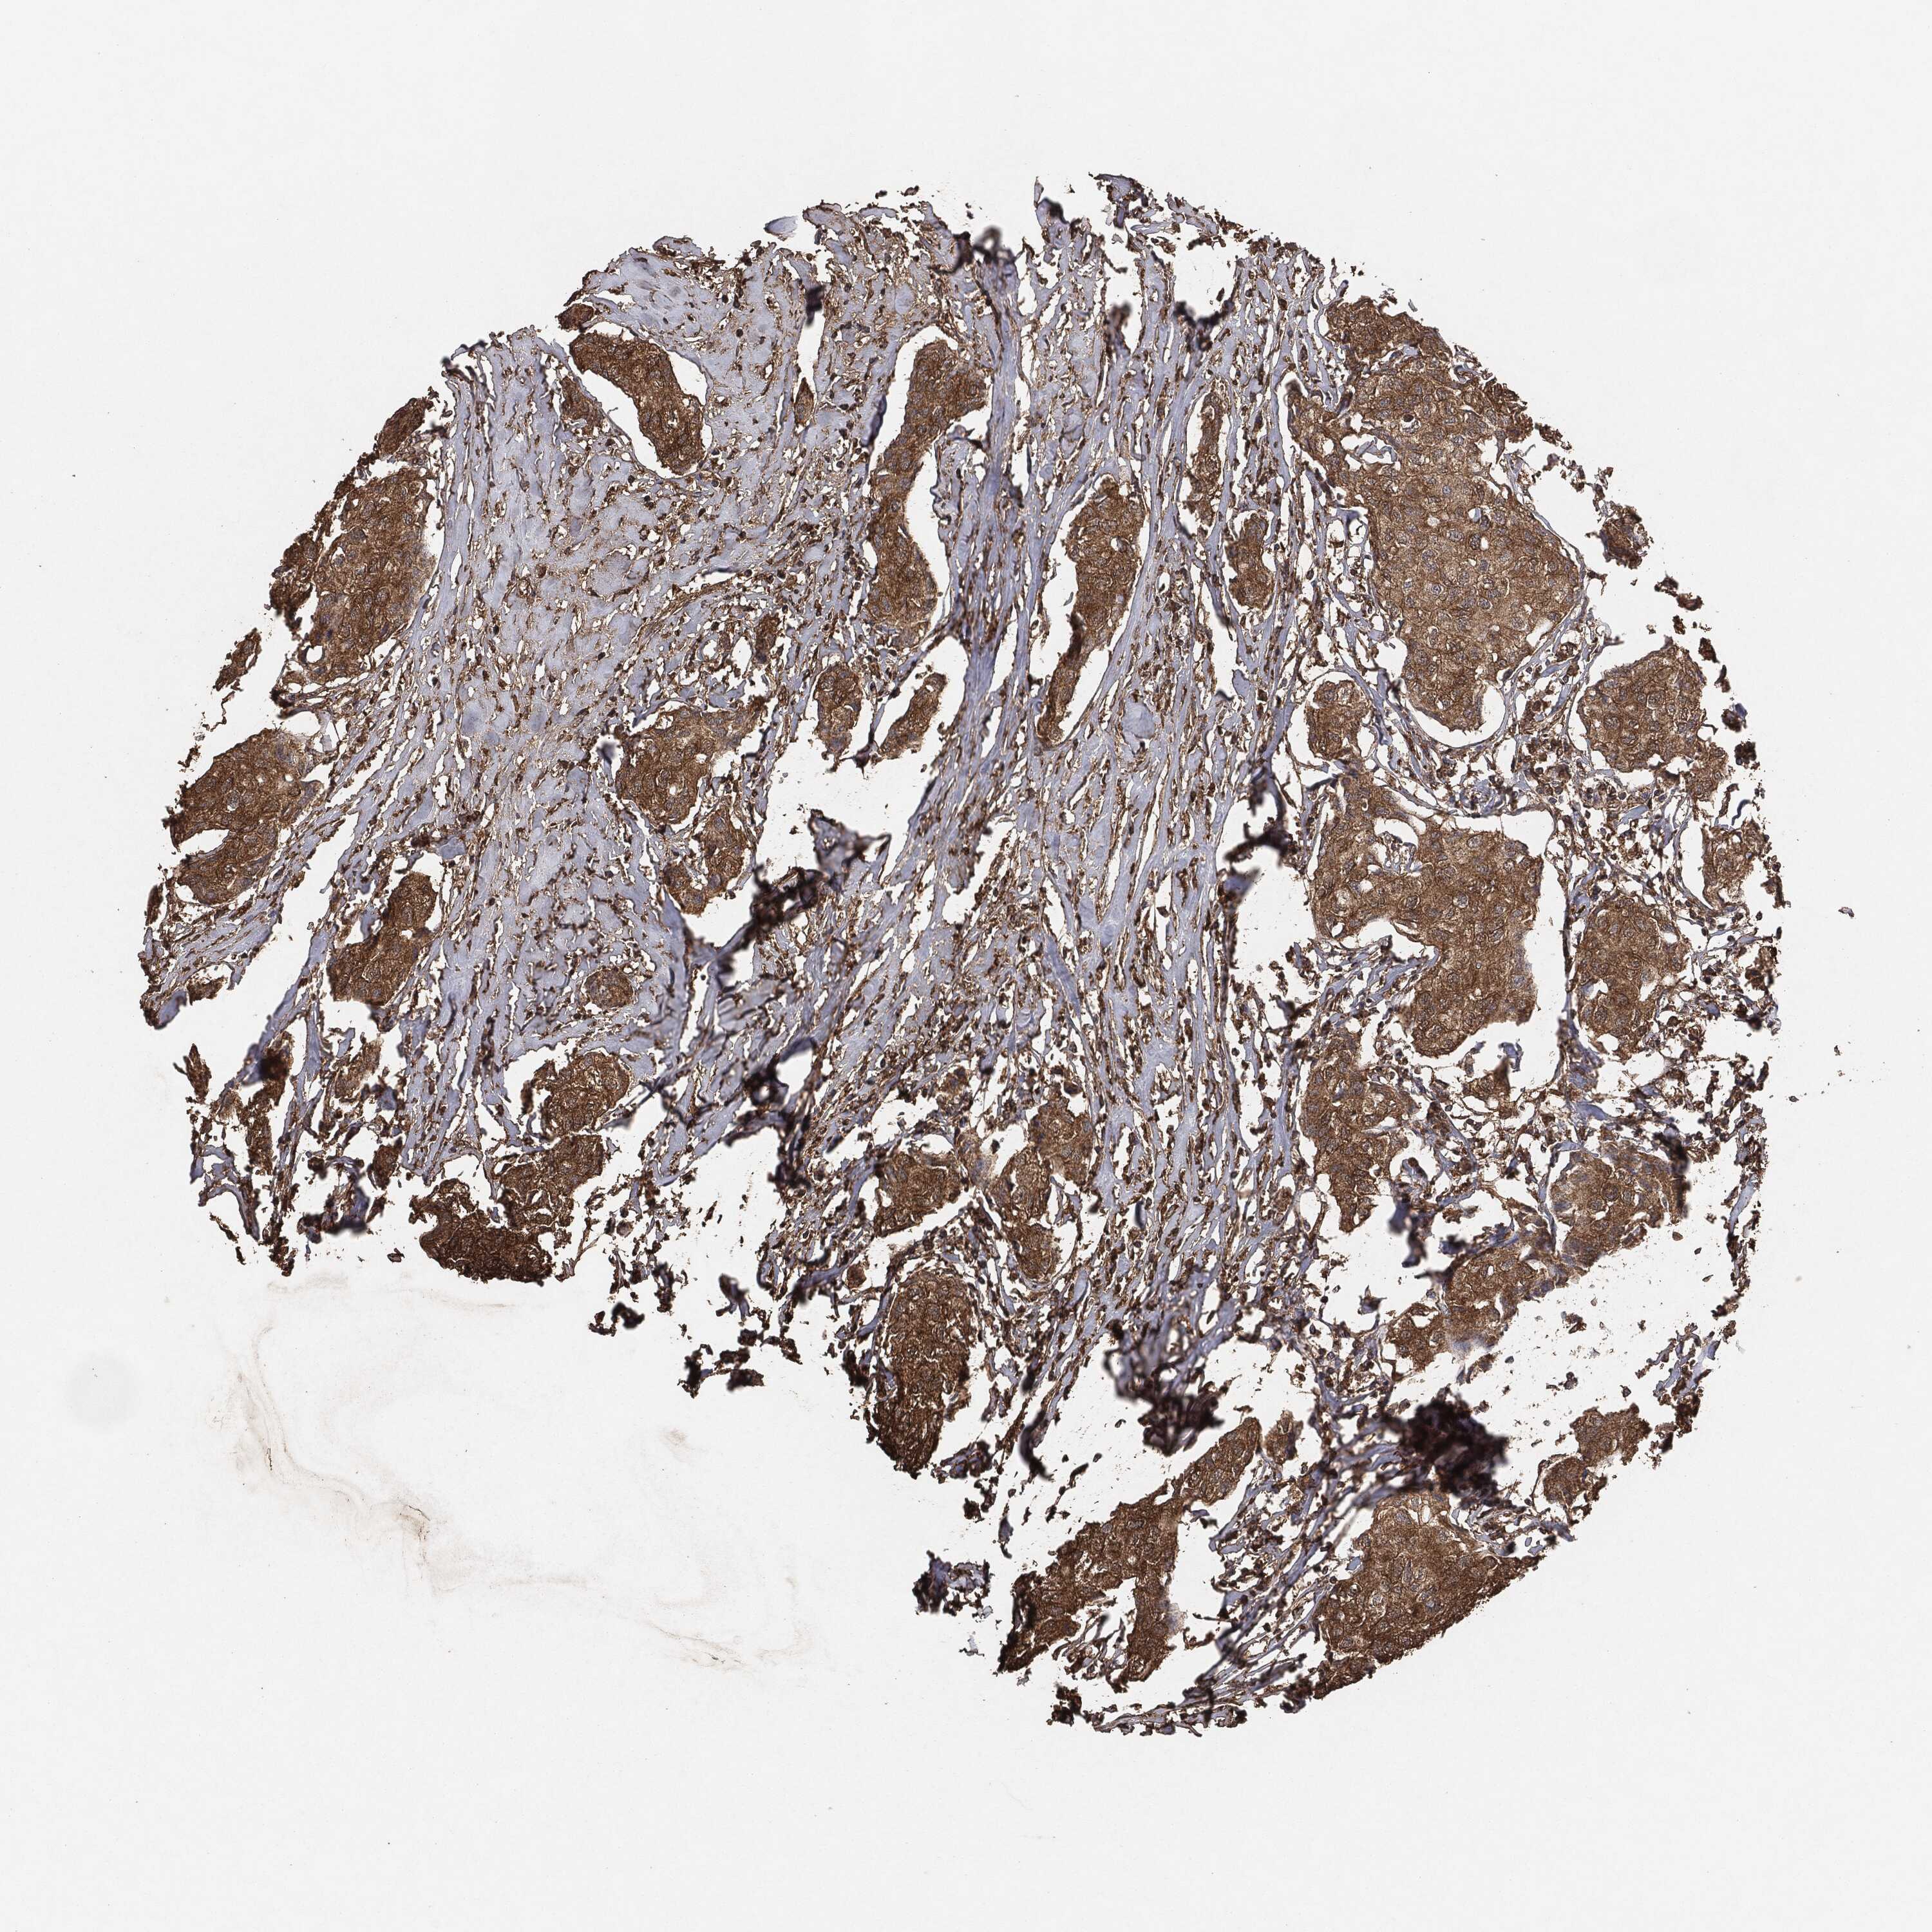

BRCA TCGA BRCA VALIDATION PROTEIN EXPRESSION

ANTIBODIES

AND

VALIDATION